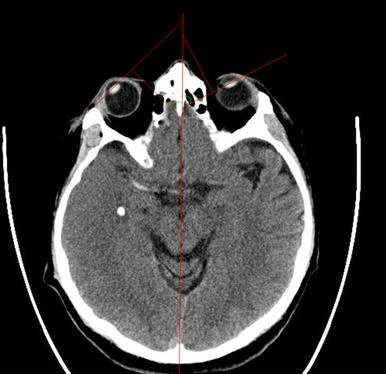

🧠1/ Have you ever felt like you're in a surreal world where sizes and scales are all warped? No, it's not a fantasy—it's a real medical condition! And our latest research dives into this mind-bending phenomenon called Alice in Wonderland Syndrome (AIWS) #Neuroscience #AIWS